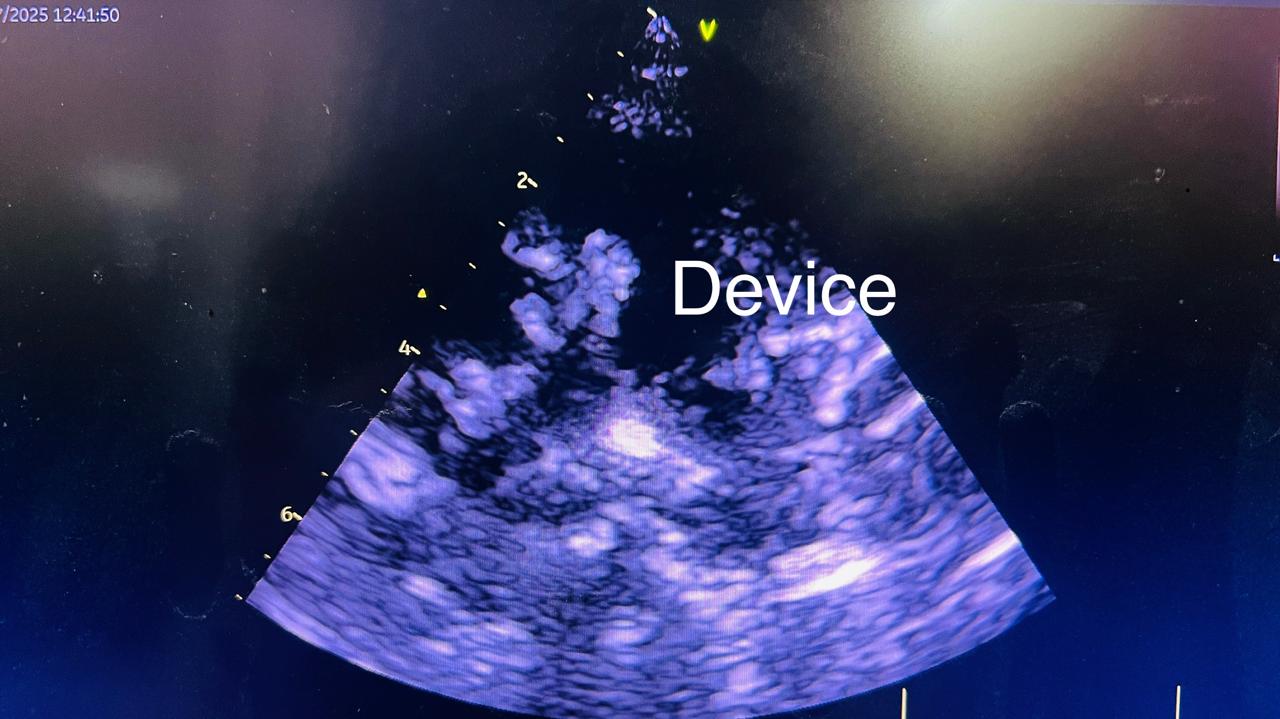

पूरी तरह से जांच करने के बाद विभागाध्यक्ष डॉ रोहित माथुर ने मरीज का इलाज ऑपरेशन के बजाय छतरी लगा कर डिवाइस क्लोजर से करने का निर्णय लिया। इसके बाद डिवाइस क्लोजर किया गया तथा रविवार को मरीज को स्वस्थ अवस्था में डिस्चार्ज कर दिया गया।

डिवाइस क्लोजर प्रोसीजर को हार्ट रोग विभाग के आचार्य डॉ रोहित माथुर, सहायक आचार्य डॉ अनिल बारूपाल, सहायक आचार्य डॉ युद्धवीर सिंह तथा मेडिकल ऑफिसर डॉ प्रदीप, एस्कॉर्ट हॉस्पिटल के डॉ नीरज अवस्थी की देख रेख में किया गया। निश्चेतना विभाग के विभागाध्यक्ष डॉ राकेश कर्णावत और डॉ भरत के सहयोग से छोटी बच्ची में निश्चेतना दी गई। हार्ट रोग विभाग के योगेश, विजय लक्ष्मी, राकेश, देवराज, नवीन, शंकर, सिमिला, जितेंद्र, रणवीर आदि नर्सिंग ऑफिसर तथा टेक्निशियन ने डिवाइस क्लोजर में महत्वपूर्ण योगदान दिया।